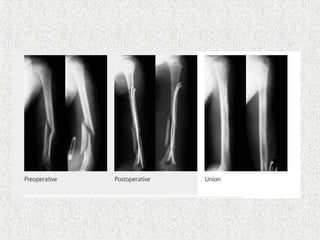

 Nail size 30-40% of isthmus diameter  Identical nail chosen to avoid valgus/varus deformity

 Insertion point 2.5-3 cm proximal to distal epiphyeal plate  One finger breadth above upper pole of patella  Avoid joint capsule & epiphysis

 The tipshould reach metaphysis  The nail’s second crossover should be after crossing # site